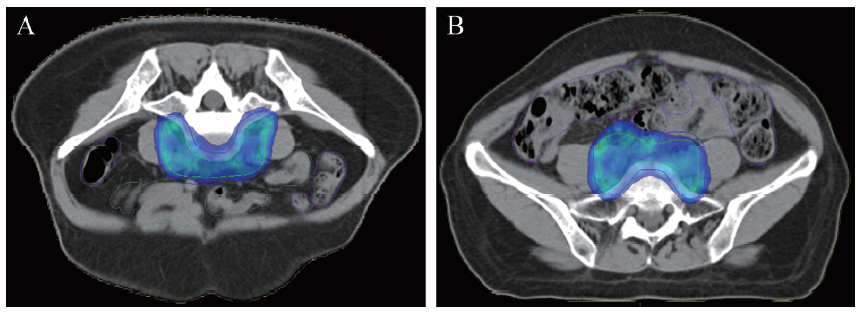

注: A为俯卧位;B为仰卧位。

二、 俯卧组与仰卧组危及器官剂量-体积比较

俯卧组患者小肠接受15~50 Gy剂量-体积(V15~V50)均比仰卧组减少,其中俯卧组的V20、V30和V40的减少有统计学意义(P均< 0.05)。俯卧组结肠V20~V50均比仰卧组下降,其中V30、V40和V45的减少有统计学意义(P均< 0.05)。俯卧组膀胱V15~V45比仰卧组稍升高,但仅V20组间比较差异有统计学意义(P < 0.05)。2组患者直肠和股骨头的剂量-体积关系比较差异均无统计学意义(P均> 0.05),见表2